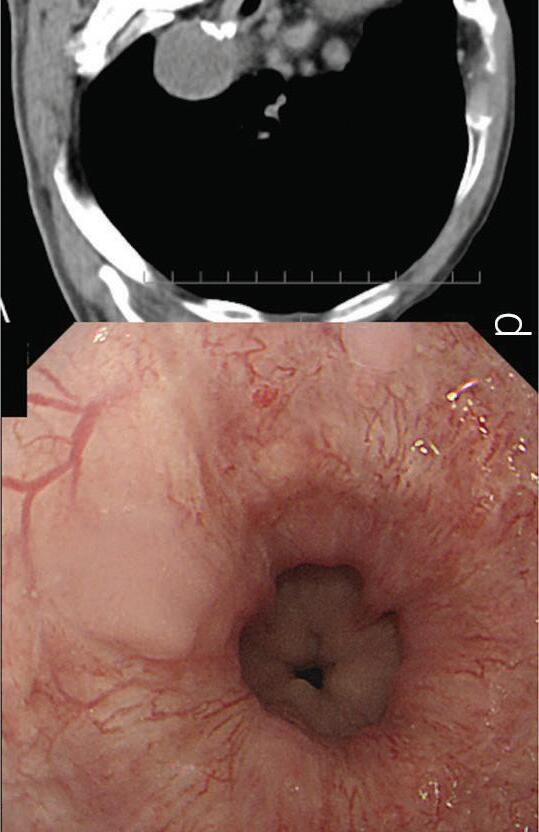

In a 1991 report in The American Journal of Gastroenterology, Drs. Alemayehu and Järnerot challenge prior orthodoxy that colonoscopy is contraindicated in patients with severe ulcerative colitis.